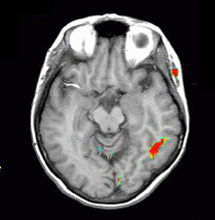

| Activación |

La activación del hemisferio izquierdo es claramente mayor. La activación se encuentra en las siguientes áreas: Área de Broca (imagen 5), área de Wernicke (imágenes 4 y 5), circunvolución supramarginal izquierda (área de asociación heteromodal, imagen 5), corteza motora y premotora izquierda. Las áreas auditivas primarias también están activadas, predominantemente en el lado izquierdo. |